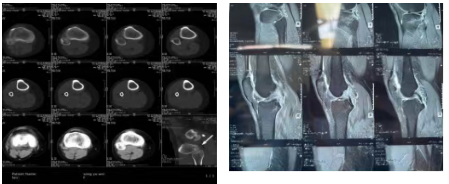

近日,36岁患者王某某因右膝扭伤后肿胀、疼痛、活动受限4小时入院。骨科团队结合病史、专科查体(侧方应力试验等)及X线、CT、MRI检查,明确诊断为右膝前交叉韧带断裂、内侧半月板撕裂、右侧胫骨平台骨折(Schatzter Ⅰ型)。

手术主要流程:1. 仰卧位气囊止血带下,取膝关节镜前内、外侧入路;2. 镜下见前交叉韧带完全断裂、内侧半月板后角撕裂、胫骨平台软骨损伤(ICRS 2级);3. 取胫骨结节内侧切口,切取并编织股薄肌、半腱肌肌腱;4. 建立股骨、胫骨隧道;5. 引入肌腱并固定(股骨侧袢钢板、胫骨侧可吸收螺钉);6. 半月板后角全内缝合;7. 缝合包扎后支具固定。